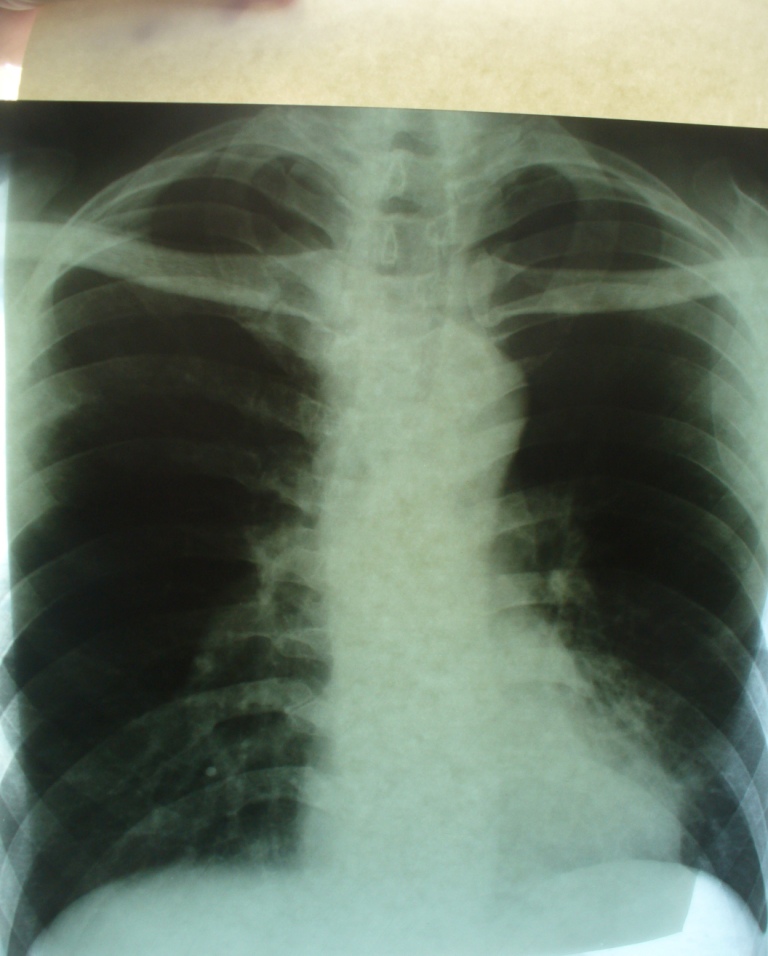

Воспалительный инфильтрат — описание болезни

Симптомы болезни Воспалительный инфильтрат

Воспалительные инфильтраты возникают как за счет контактного распространения инфекции (per continuitatum), так и лимфогенного пути при поражении лимфатического узла с дальнейшей инфильтрацией тканей. Инфильтрат обычно развивается в течение нескольких дней. Температура у больных бывает нормальной и субфебрильной. В области поражения возникают припухлость и уплотнение тканей с относительно четкими контурами и распространением на одну или несколько анатомических областей. Пальпация безболезненная или слабо болезненная.

Флюктуация не определяется. Кожные покровы в области очага поражения обычной окраски или слегка гиперемированы, несколько напряжены. Имеет место поражение всех мягких тканей данной области — кожи, слизистой оболочки, подкожно-жировой и мышечной ткани, нередко нескольких фасций с включением в инфильтрат лимфатических узлов. Именно поэтому мы отдаем предпочтение термину «воспалительный инфильтрат» перед термином «целлюлит», которым также обозначают подобные поражения. Инфильтрат может разрешаться в гнойные формы воспаления — абсцессы и флегмоны и в этих случаях его следует рассматривать как предстадию гнойного воспаления, которую не удалось купировать.

Диагностика болезни Воспалительный инфильтрат

Дифференциальную диагностику воспалительного инфильтрата проводят с учетом выявленного этиологического фактора и давности заболевания. Диагноз подтверждают нормальная или субфебрильная температура тела, относительно четкие контуры инфильтрата, отсутствие признаков гнойного расплавления тканей и резкой болезненности при пальпации. Другими, менее выраженными, отличительными признаками служат: отсутствие значительной интоксикации, умеренная гиперемия кожного покрова без выявления напряженной и лоснящейся кожи. Таким образом, воспалительный инфильтрат может характеризоваться преобладанием пролиферативной фазы воспаления мягких тканей челюстно-лицевой области. Это, с одной стороны, свидетельствует об изменени реактивности организма ребенка, с другой — служит проявлением естественного и терапевтического патоморфоза.